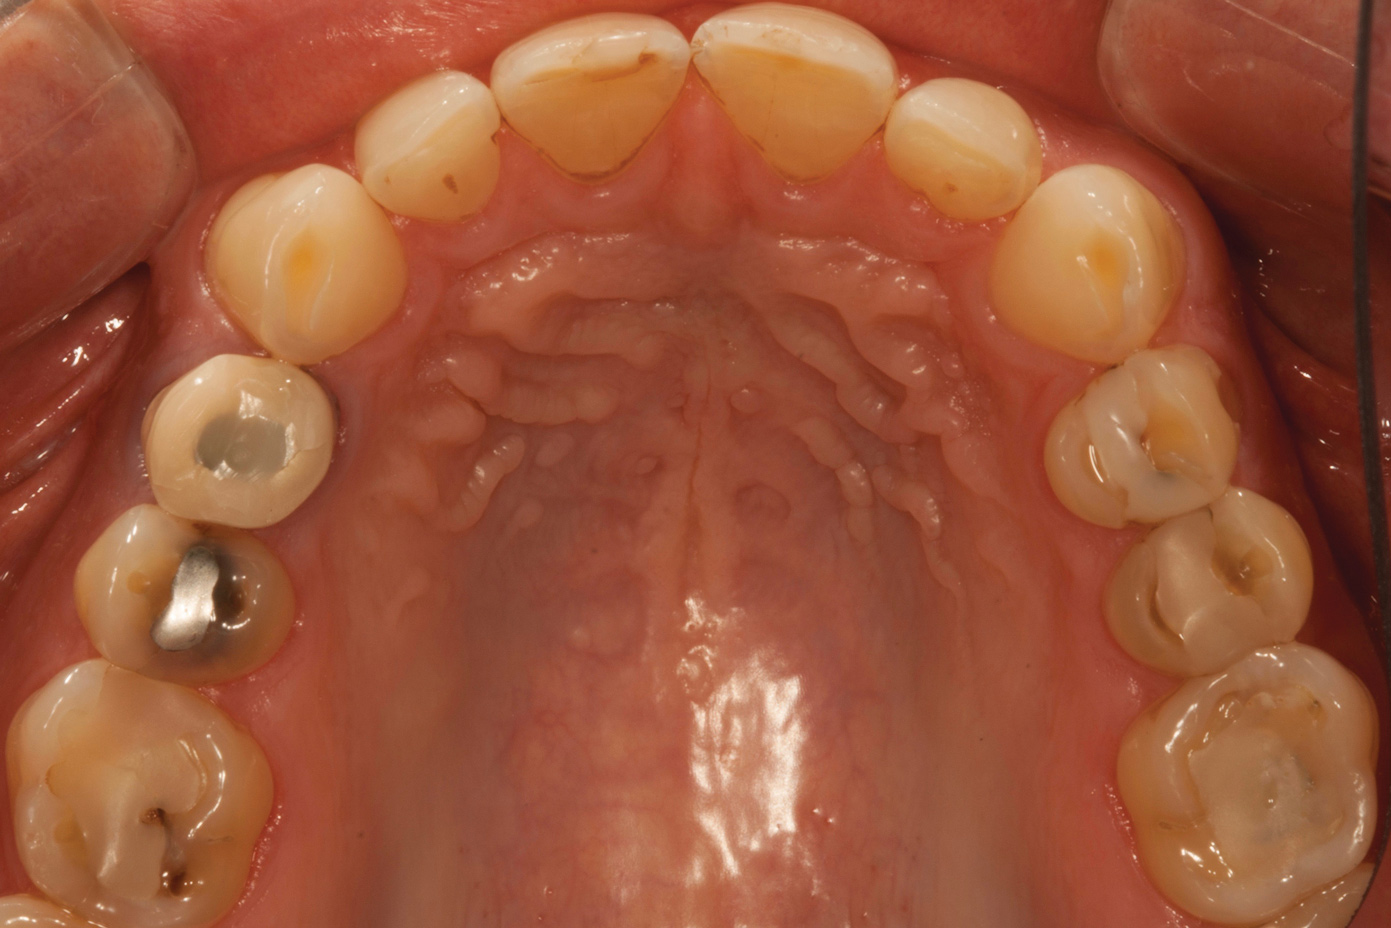

A 34-year-old male patient with no medical issues presented to the office with the chief complaint of a failing crown on tooth No. 12. The patient was also unhappy with his bite and the appearance of his teeth (Figure 1 and Figure 2).

A comprehensive examination was carried out, and preoperative photographs were taken (Figure 1 through Figure 4). The patient presented with fair oral hygiene and slight, generalized tissue inflammation. Caries and defective restorations were detected on teeth Nos. 4, 5, 13, and 14. The crown on tooth No. 12 was showing signs of leakage, and although the endodontic access cavity had been temporarily restored with composite, this endodontic re-treatment was acceptable and the tooth was otherwise symptom-free. Erosion was present on most of the posterior teeth and the cuspids, and abrasion was noted on teeth Nos. 4, 5, 10, 11, 20, 21, 22, 28, and 29. An examination of the patient's muscles, joints, and bite revealed no joint sounds, a normal range of motion, and negative joint load and immobilization tests.

Fig 4. Preoperative occlusal view of upper arch.

Figure 4